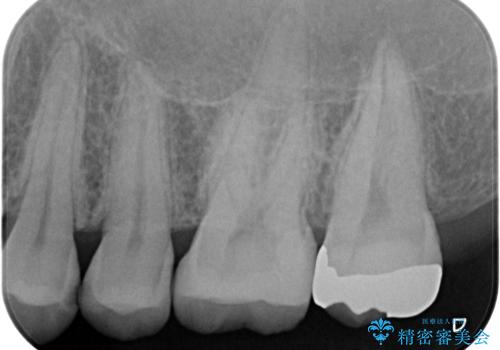

- 銀歯のやり替えと虫歯の治療をご希望で来院された患者様です。

一番奥の歯は外から見えにくい部分であるためゴールドインレーで修復します。

その他はセラミックインレーで修復します。

- 左上46:セラミックインレー/77,000円×2 左上7:ゴールドインレー/77,000円×1費用は治療当時の料金となります

噛みしめの強い方や、外から見えないような部分では、割れる心配のないゴールドインレーをおすすめします。